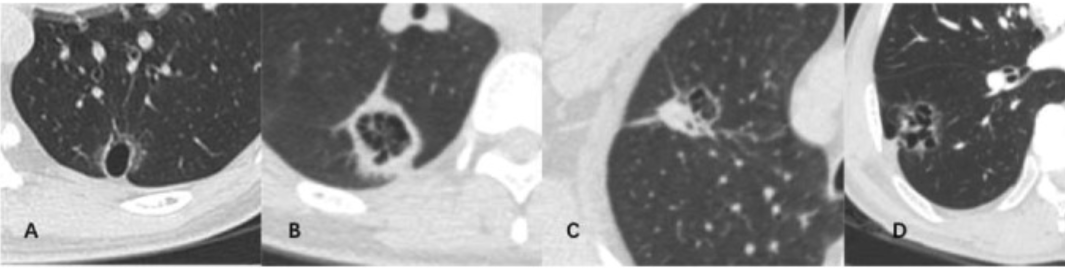

kyste cyst lung tumor tumeur adénocarcinome cancer lésion kystique cystic enlargement suspect classe classification

kyste cyst lung tumor tumeur adénocarcinome cancer lésion kystique cystic enlargement suspect classe classification